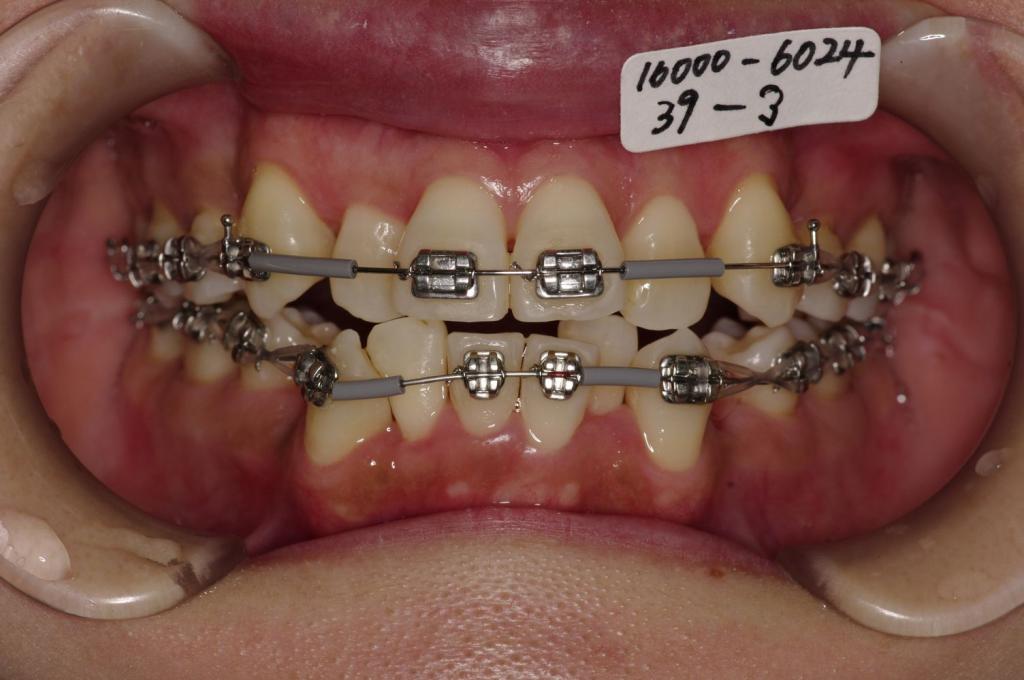

装置の種類及び治療法 診断:叢生 上下顎前突

治療方法および装置:マルチブラケット装置

High pull J-hook headgear

抜歯:右上84 /左上48

右下4 /左下4

欠損歯:右上8 /左上8

右下 /左下

治療期間:16ヶ月

装置写真

治療前

歯並び・咬み合わせ・八重歯・乱杭歯の矯正治療前口内写真NO.1212